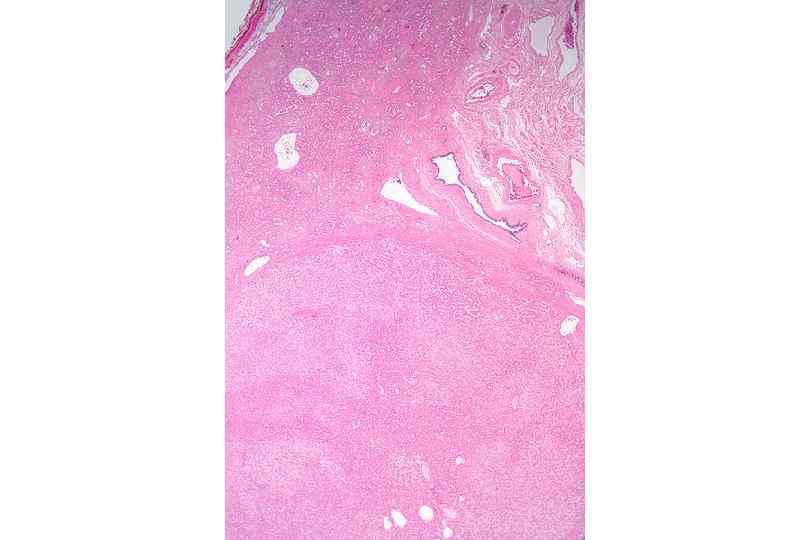

• Печень. × 10 (H&E). в цирротических узлах выраженная паренхиматозная дистрофия гепатоцитов с внутриядерными включениями; участки выраженного ядерно цитоплазматического изменения; фокальные очаги микростеатоза. Признаки холестаза желчных протоков. ЦИРРОЗ (жировая дистрофия + фиброз + полнокровие)– на фоне застоя в центральной вене печёночных долек формируются внутридольковые и междольковые сосудистые шунты с ретроградным током крови; интоксикация.